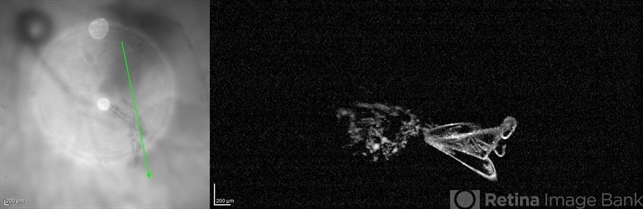

- vitreous floaters, black floaters

- OCT scan of a vitreous floater in a 42- year-old male after anti-VEGF injection.